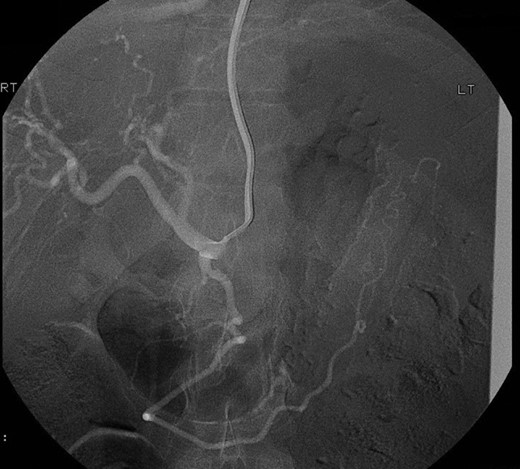

However, 4 days after the ultrasound guided injection, the patient collapsed on the ward with haematemesis and hypovolaemic shock. He was resuscitated initially with intravenous fluids and transfusion of blood products and remained alert with no abdominal signs. An emergency gastroscopy showed a 1.5 cm gastric ulcer on the posterior gastric wall with a large clot in the upper stomach but no active bleeding. A repeat CT abdomen demonstrated persistent flow in the pseudoaneurysm (Fig. 4).

CT abdomen image post thrombin injection shows flow in the pseudoaneurysm (arrow).